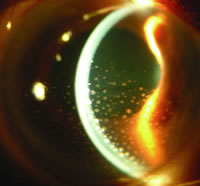

(2)角膜後沉著物

炎症細胞或色素沉積於角膜後表面,被稱為KP。其形成需要角膜內皮損傷和炎症細胞或色素的同時存在。根據KP的形狀,可將其分為三種類型,即塵狀、中等大小和羊脂狀。前兩種主要由中性粒稀薄、淋巴細胞和漿細胞沉積而成,後者則主要由單核巨噬細胞核類上皮構成。塵狀KP主要見於非肉芽腫性葡萄膜炎;中等大小KP主要見於Fuchs綜合徵和單皰病毒性角膜炎伴發的片葡萄膜炎;羊脂狀KP主要見於肉芽腫性前葡萄膜炎。

KP有三種分布類型,即:

①下方的三角形分布:是最常見的一種分布形式,見於多種類型的前葡萄膜炎;

②角膜瞳孔區分布:主要見於Fuchs綜合徵、青睫綜合徵和單皰病毒性角膜炎伴發的前葡萄膜炎;

③角膜後瀰漫性分布:主要見於Fuchs綜合徵和單皰疹病毒性角膜炎伴發的前葡萄膜炎。